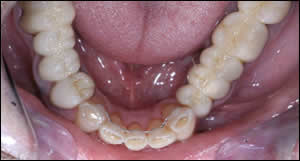

Fig 11: Total treatment time was 3 months for the maxillary teeth. Splinted interim acrylic crowns were placed on the maxillary anterior teeth to achieve golden proportions...and to provide retention. Treatment time was 6 months for the mandibular teeth. The alignment of the mandibular anterior teeth allowed for the proper contour and sagital position of the upper incisors. A normal overbite/overjet relationship was established. A bonded lingual retainer was placed on the lower anterior teeth.